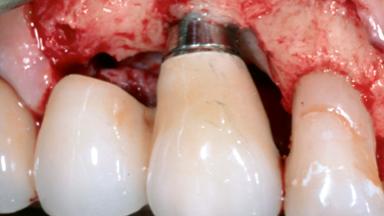

Replacement of a Failing Upper Right Central Incisor, Ridge Preservation and Late Placement of a NC Bone Level Implant

A 30-year-old patient presented at our clinic with a chief complaint of pain in her endodontically treated right maxillary central incisor (tooth 11) with a post-and-core and a fixed single crown. She had a very high lip line, a medium to thin soft-tissue phenotype, and a medium scalloped gingival contour. She also had high esthetic expectations because of her young age and beautiful smile. However, her expectations were realistic and she understood the risks of the treatment. At the initial clinical examination there was a slight mobility of tooth 11; no fistula was observed. The patient also had a single crown on the adjacent tooth 21. Both restorations were old and esthetically deficient. A digital periapical radiograph showed a very small periapical radiolucency, a thick intraradicular post, and no separation between root fragments.